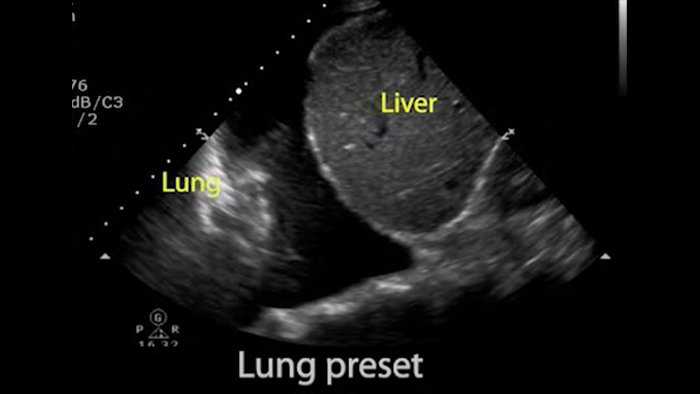

Lumify POCUS solutions can help you detect the endotracheal tube within the trachea, assist in emergent cricothyrotomy procedures, diagnose pleural effusion and interstitial alveolar diseases.

• 4 to 1 MHz extended operating frequency range • 2D, color Doppler, M-mode, advanced XRES and multivariate harmonic imaging • High-resolution imaging for abdominal and cardiac applications: Cardiac, OB/GYN, Lung, Abdomen and FAST imaging preset optimizations